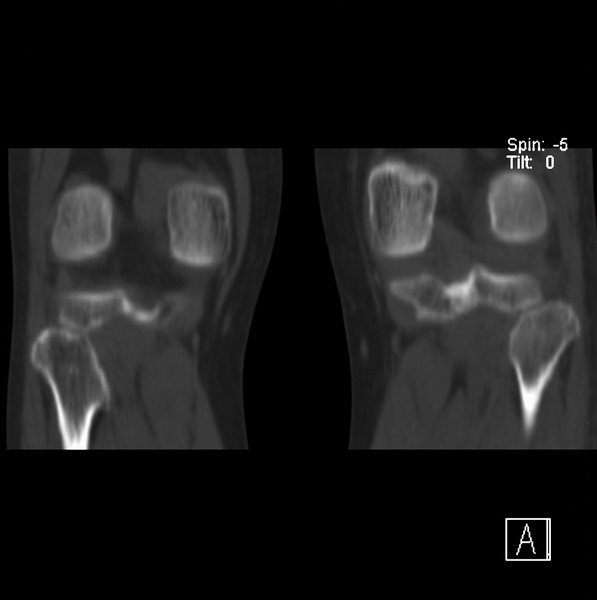

标题: CT21917:右腓骨小头是否骨软骨瘤? [打印本页]

标题: CT21917:右腓骨小头是否骨软骨瘤?

女、43.

不是骨软骨瘤,“牵拽征”,正常变异。有平片吗?

正常变异,“牵拽征”,比目鱼肌牵拽.

比目鱼肌附着点